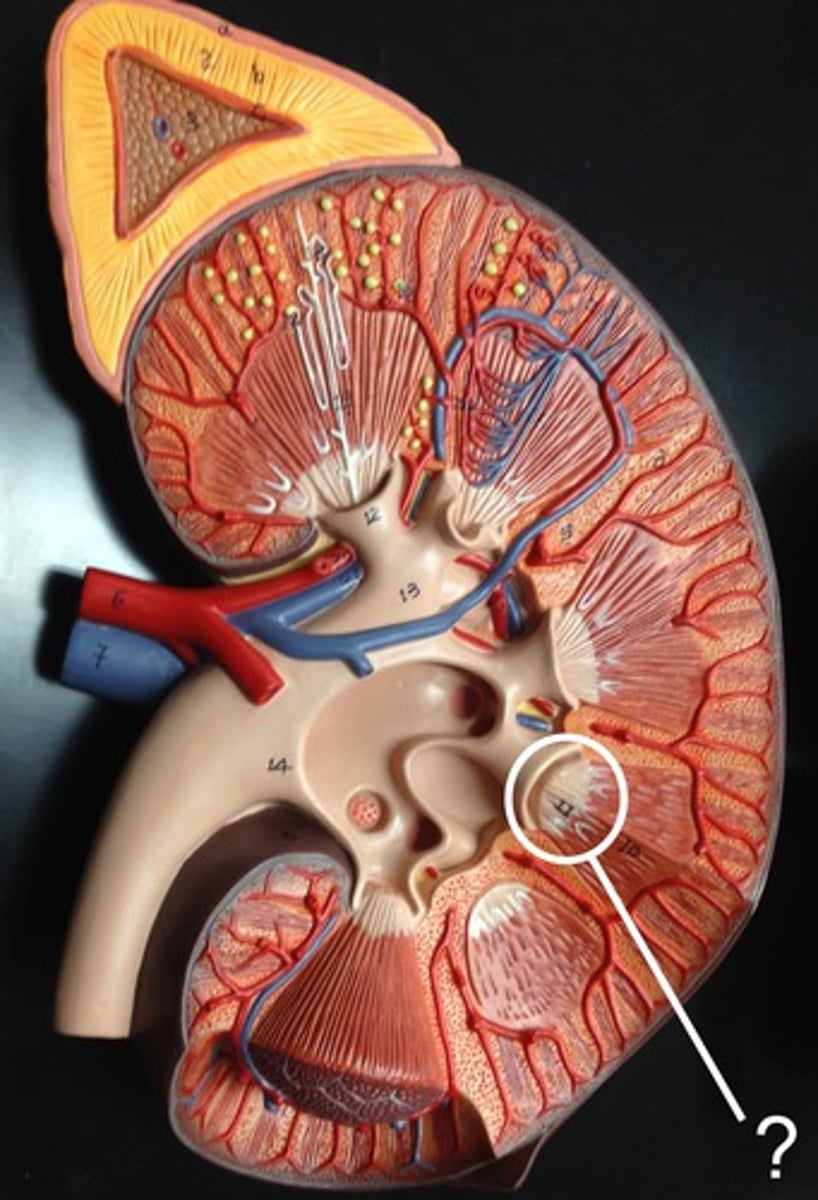

minor calyx

cup that nestles the papilla of each pyramid; collects its urine

major calyx

urine passageway

renal pelvis

central collecting region in the kidney